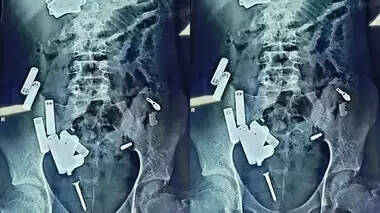

ജയ്പൂരിലെ ആശുപത്രിയിലേക്ക് റഫർ ചെയ്തു. ടെസ്റ്റുകൾക്ക് ശേഷം ഒക്ടോബർ 19ന് യു.പിയിലേക്ക് മടങ്ങി. രണ്ട് ദിവസത്തിന് ശേഷം, വീണ്ടും അസുഖം കൂടി. അലിഗഡിൽ നടത്തിയ സി.ടി സ്കാനിൽ മൂക്കിലുണ്ടായ തടസം കണ്ടെത്തുകയും ചികിത്സിക്കുകയും ചെയ്തു. പിന്നാലെ ആദിത്യയ്ക്ക് വയറുവേദന തുടങ്ങി. 26ന് അലിഗഡിൽ അൾട്രാസൗണ്ട് പരിശോധന നടത്തി. ഇതിലാണ് 19 വസ്തുക്കൾ വയറിനുള്ളിൽ കുടുങ്ങിയതായി കണ്ടെത്തിയത്. ഉടൻ തന്നെ കുട്ടിയെ നോയിഡയിലെ ഒരു സ്വകാര്യ ആശുപത്രിയിലേക്ക് റഫർ ചെയ്തു. നോയിഡയിൽ ഡോക്ടർമാർ നടത്തിയ പരിശോധനയിൽ കുട്ടിയുടെ വയറ്റിൽ 42 വസ്തുക്കൾ കണ്ടെത്തി. തുടർന്ന് അടിയന്തര വൈദ്യസഹായത്തിനായി ആദിത്യയെ ഡൽഹിയിലെ സഫ്ദർജംഗ് ഹോസ്പിറ്റലിലേക്ക് മാറ്റി. അവിടെ സ്കാനിംഗിൽ ആകെ 65 വസ്തുക്കളുണ്ടെന്ന് സ്ഥിരീകരിച്ചു. ഇതിനിടെ കുട്ടിയുടെ ഹൃദയമിടിപ്പ് മിനിറ്റിൽ 280 ആയി ഉയർന്നു.

തുടർന്ന് നടത്തിയ പരിശോധനയ്ക്കൊടുവിൽ ശസ്ത്രക്രിയ നടത്താൻ തീരുമാനിക്കുകയായിരുന്നു.സാധനങ്ങൾ കുട്ടി വിഴുങ്ങിയതാകാനാണ് സാദ്ധ്യതയെന്ന് ആശുപത്രി അധികൃതർ അറിയിച്ചു. കുട്ടിക്ക് കുടലിൽ അണുബാധയുണ്ടായിരുന്നു.